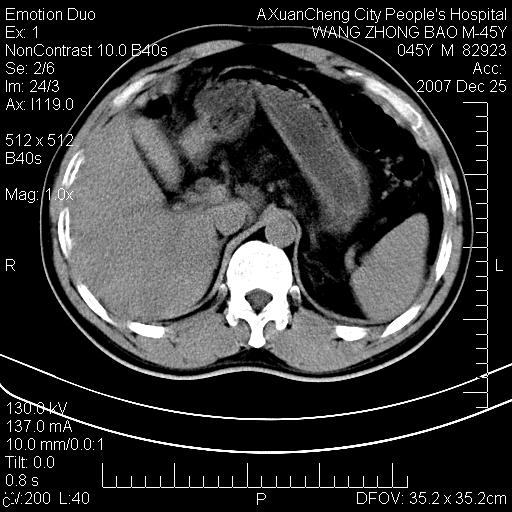

以下是引用qiuleiyu在2007-12-25 18:14:00的发言:[br]胰腺增大,周边渗出改变,肾前筋膜明显增厚,示少量积液.胆囊壁毛糙,周边少许渗出,胆总管壁厚,异常强化,然扩张不明显.结合病程急短;考虑;胆管炎,胆囊炎,胆源性胰腺炎可能大,请结合实验室检查及随访.

以下是引用lisihao在2007-12-25 14:23:00的发言:[br]急性水肿型胰腺炎[br]依据:1、胰腺弥漫性肿大,边缘稍毛糙;[br] 2、双侧肾周筋膜增厚,尤以左侧为甚(重要征象)[br] 3、双侧后胸膜增厚(刺激性炎症);[br] 4、结合病史,查血尿淀粉酶应该可以确诊。